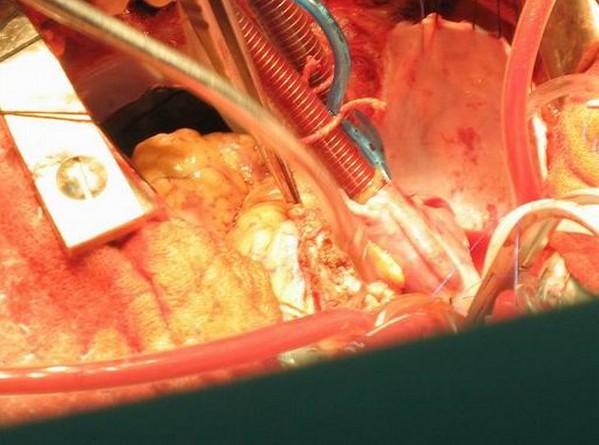

冠脉和颈动脉造影:术中发现LCX远端、其近段发出一心房支向瘤体供血,在右心房后方有血供丰富的瘤体。右侧颈总动脉分叉后方和左侧颈总动脉分叉前方有肿瘤显影,血供丰富。

分两次手术切除颈部及心脏部位的肿物, 大体病理及免疫组化均支持嗜铬细胞瘤的诊断。

两例患者的异位嗜铬细胞瘤除了上述特点以外还有自己的特点,1) 它生长的部位为主动脉根部或心脏表面,由冠状动脉供血或累及冠状动脉;2)肿瘤的部位紧邻主动脉根部、冠状动脉和主肺动脉,使肿瘤的切除变得十分困难;3)肿瘤的高分泌症状(高血压、心悸、多汗、头疼)明显,特别是血压和心率的波动更容易受到影响。

手术成功治疗切除异位嗜铬细胞瘤。